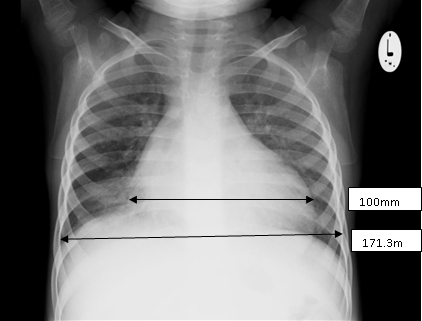

Diagnosis: The child may present with features of heart failure with evidence of cardiomegaly demonstrable on clinical examination, chest x-ray and electrocardiogram.

Echocardiographic findings include left ventricular (LV) dilatation, global hypokinesia and a reduced LV ejection fraction. Mitral and tricuspid regurgitation due to annular dilation may also be present.